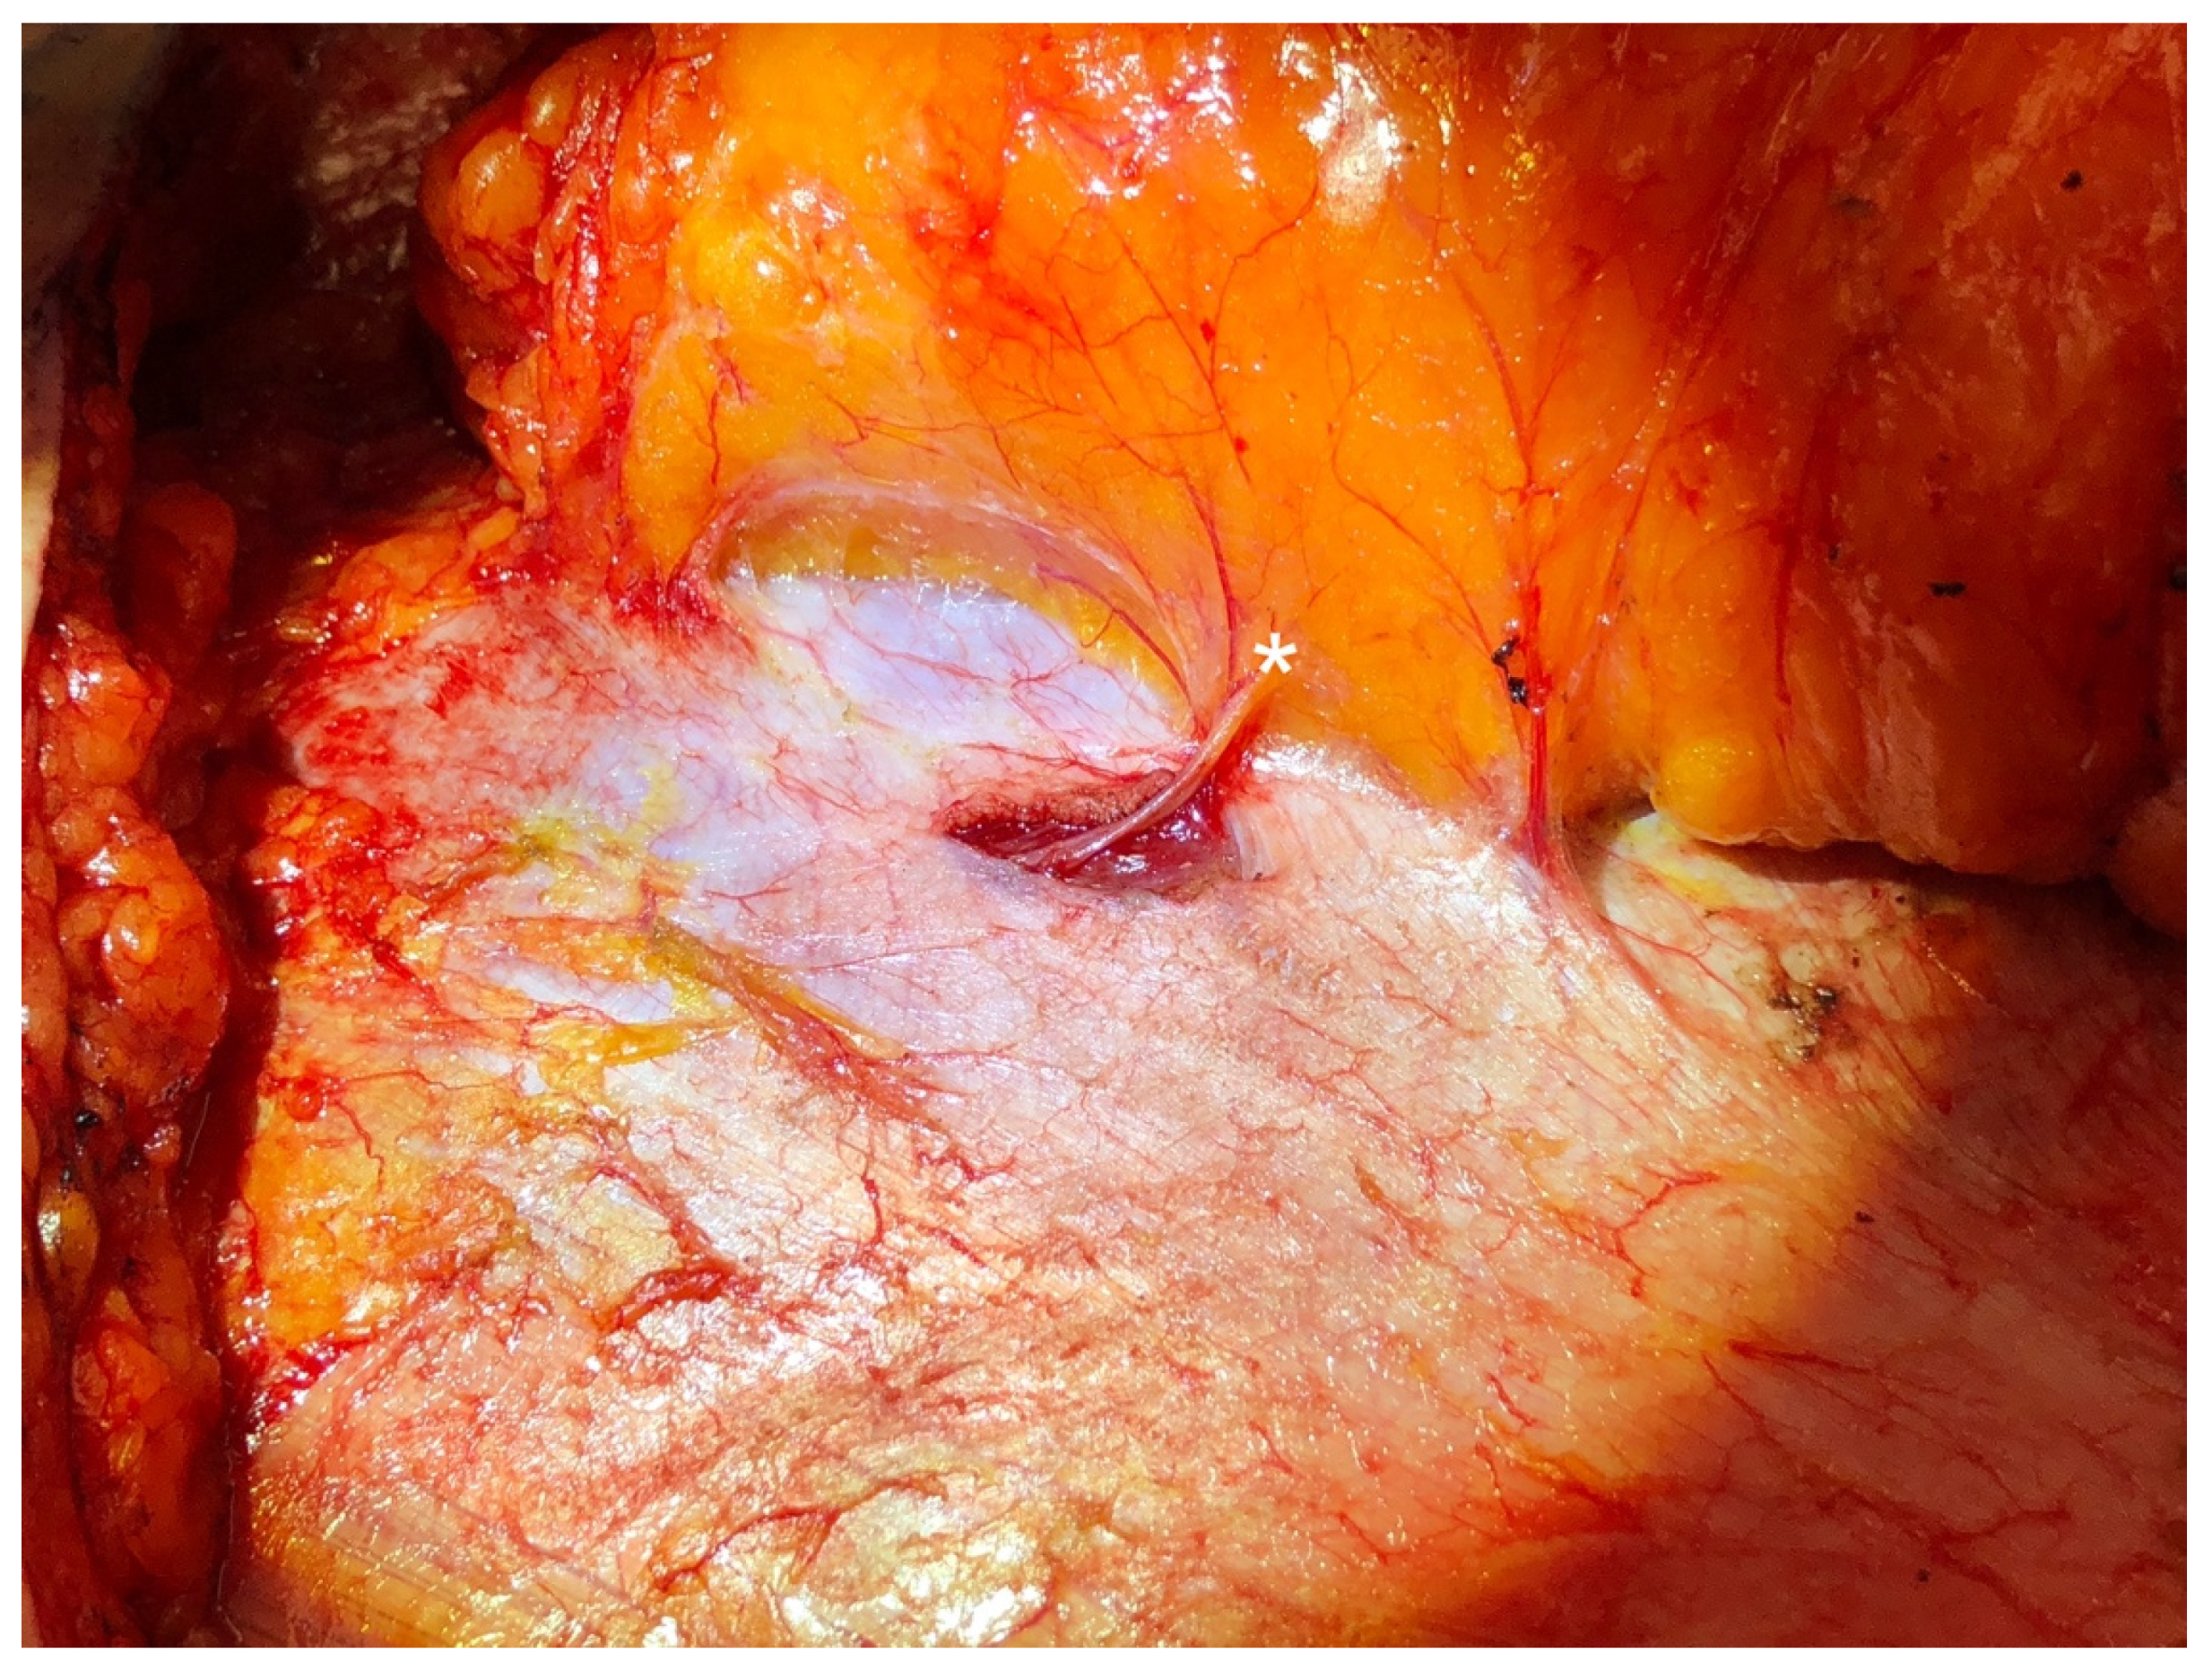

In this technique, sensory nerves are identified traveling with lateral row perforating vessels toward the skin during standard abdominal flap elevation. If the flap is to be based on lateral row vessels, the anterior rectus sheath is incised in line with these perforators, as is commonly performed in DIEP flap harvest. Retrograde dissection of a centrally located sensory nerve is performed until a sensory–motor Y-junction is encountered, typically representing a bifurcation of ICN 11 or 12. The sensory branch is clipped and divided distal to the Y-junction, thus, preserving the motor branch to the rectus abdominis muscle. If the flap is based on medial perforators, a lateral sensory nerve branch is isolated and harvested via a separate 5 mm incision in the fascia (Figure 1), which is closed with a single figure-of-eight stitch [47,53,56]. The rest of flap elevation and pedicle dissection proceed in standard fashion.

Figure 1.

A sensory intercostal nerve branch (denoted by the asterisk) that is not traveling with the dominant perforating vessels is harvested via a short separate fascial incision during abdominal flap elevation.